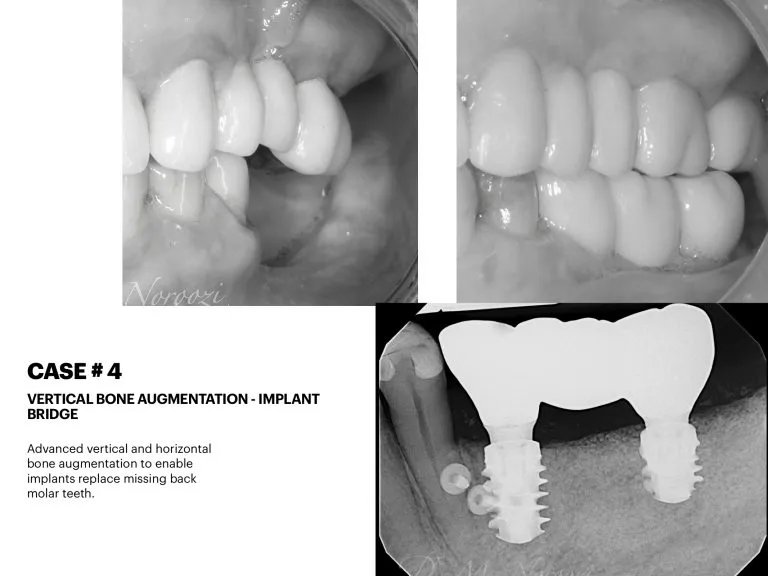

Before & Afters of Dental Implant Patients

Complete Dental Implant Cases Gallery

If you are in good general health, have healthy gums, and have enough bone in the jaw to hold an implant, dental implants might be right for you. If your jawbone has shrunk or if it has not developed normally, you may be able to have a bone graft to build up the bone. A bone graft is a way of adding new bone to your jawbone. Your dentist or dental specialist will tell you if bone grafting can be done.

• When replacing several teeth or all of your teeth, a fixed bridge is anchored to your dental implants. A bridge is a dental restoration that replaces one or more missing teeth by spanning an area that has no teeth. The bridge is held firmly in place by dental implants on each side of the missing tooth or teeth.

General Disclaimer: The results in the photographs are examples only and do not imply any certainty of the result of a procedure, and all outcomes are subject to the circumstances of the individual patient.